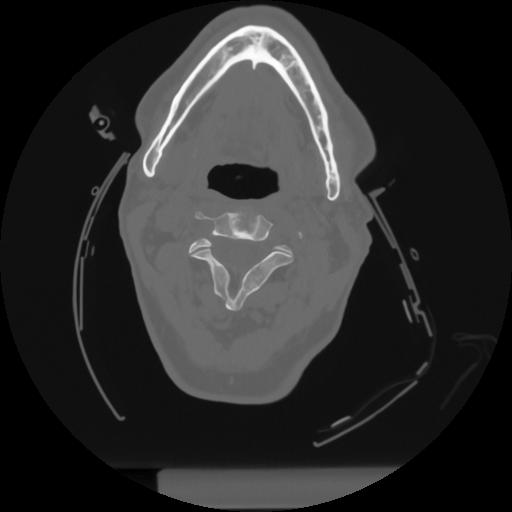

12 P.BLANDAS,,Vol,0.5,P.BLANDAS,,